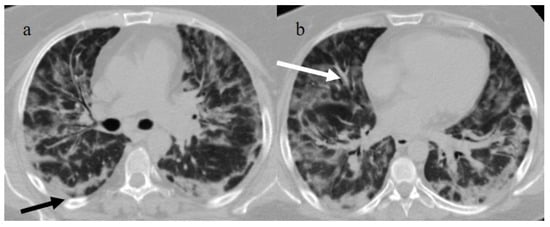

3.3.1. Acute Respiratory Distress Syndrome

| Typical Appearance | GGOs with a crazy-paving pattern and consolidations in a peripheral and posterior or central-peripheral distribution; multilobar involvement; vascular enlargement, the halo and reversed halo sign; subpleural and parenchymal bands; and architectural distortion. They were predominant since the Delta wave. |

| Typical findings of interstitial pneumonia with peripheral or peripheral central distribution from the wild/type variant since Delta variant |